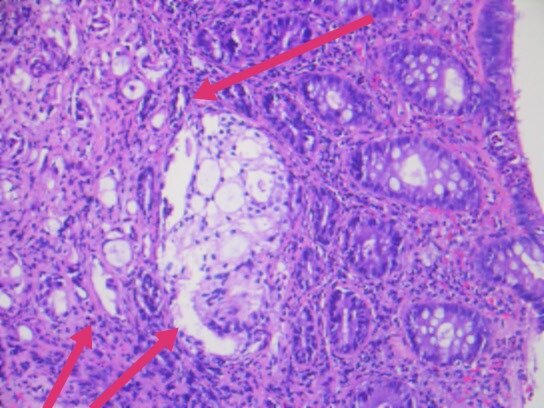

几天前,入我院行肠镜检查,并活检,显微镜下可见癌浸润于直肠粘膜之间。

最终,我们以上述HE形态为线索,老年男性,直肠占位,为XY坐标,我们初步音箱诊断就是前列腺腺泡腺癌浸润至前列腺腺外,累及直肠并形成肿块,浸润直肠全层至粘膜内。